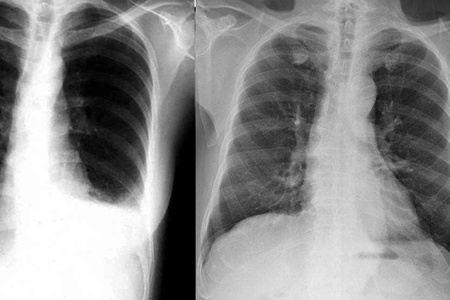

支气管肺癌的症状其实非常明显,如果是在癌症的早期,主要表现为咳嗽,痰中有血,有的患者会有气短等等症状,这个时候患者就需要到医院做一个胸外科检查,及时发现疾病。而到了中后期之后,患者的症状会明显加强,比如说咳嗽得更加剧烈,甚至会有呕血的现象,而且胸部会出现疼痛,气短也会更加严重,甚至爬一个小小的楼梯都会气喘吁吁。